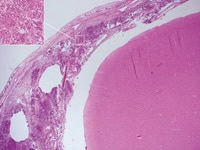

Histopathology of bacterial Meningitis: autopsy case of a patient with pneumococcal meningitis showing leptomeningeal inflammatory infiltrates consisting of neutrophilic granulocytes (inset, higher magnification). Hematoxylin-Eosin stain Credit Wikipedia/Marvin 101